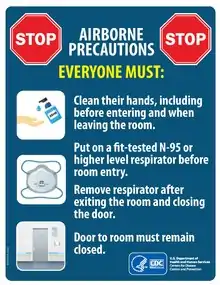

- On 6 July, Morawska and aerosol scientist Donald Milton at the University of Maryland, College Park, supported by an international group of 237 other clinicians, infectious-disease physicians, epidemiologists, engineers and aerosol scientists, published a commentary in the journal Clinical Infectious Diseases that urges the medical community and public-health authorities to acknowledge the potential for airborne transmission. They also call for preventive measures to reduce this type of risk.

The researchers are frustrated that key agencies, such as the World Health Organization (WHO), haven’t been heeding their advice in their public messages.

In response to the commentary, the WHO softened its position. At a 7 July press conference, Benedetta Allegranzi, technical leader of the WHO task force on infection control said: “We have to be open to this evidence and understand its implications regarding the modes of transmission, and also regarding the precautions that need to be taken.”

On 9 July, the WHO issued a scientific brief on viral transmission. It maintains that more research is needed “given the possible implications of such [a] route of transmission”, but acknowledges that short-range aerosol transmission cannot be ruled out in crowded, poorly ventilated spaces. (The WHO told Nature that it had been working on this brief for a month, and that it was not a result of the commentary.) - For months, the WHO had steadfastly pushed back against the idea that there is a significant threat of the coronavirus being transmitted by aerosols that can accumulate in poorly ventilated venues and be carried on air currents. The agency maintains that the virus is spread mainly by contaminated surfaces and by droplets bigger than aerosols that are generated by coughing, sneezing and talking. These are thought to travel relatively short distances and drop quickly from the air.

This type of guidance has hampered efforts that could prevent airborne transmission, such as measures that improve ventilation of indoor spaces and limits on indoor gatherings, say the researchers in the commentary: “We are concerned that the lack of recognition of the risk of airborne transmission of COVID-19 and the lack of clear recommendations on the control measures against the airborne virus will have significant consequences: people may think that they are fully protected by adhering to the current recommendations, but in fact, additional airborne interventions are needed for further reduction of infection risk.” - Since the 1930s, public-health researchers and officials have generally discounted the importance of aerosols — droplets less than 5 micrometres in diameter — in respiratory diseases such as influenza. Instead, the dominant view is that respiratory viruses are transmitted by the larger droplets, or through contact with droplets that fall on surfaces or are transferred by people’s hands. When SARS-CoV-2 emerged at the end of 2019, the assumption was that it spread in the same way as other respiratory viruses and that airborne transmission was not important.

The WHO is following the available evidence, and has moderated its earlier opposition to the idea that the virus might spread through aerosols, Allegranzi says. She says that although the WHO acknowledges that airborne transmission is plausible, current evidence falls short of proving the case. She adds that recommendations for physical distancing, quarantine and wearing masks in the community are likely to go some way towards controlling aerosol transmission if it is occurring. - When SARS-CoV-2 emerged, health officials recommended frequent hand washing and maintaining a physical distance to break droplet and contact transmission routes. And some researchers and clinicians say these approaches are enough. Contact-tracing data support those measures, says Kate Grabowski, an infectious-disease epidemiologist at Johns Hopkins University in Baltimore, Maryland. “The highest-risk contacts are those that are individuals you share a home with or that you’ve been in a confined space with for a substantial period of time, which would lead me to believe it’s probably driven mostly by droplet transmission,” she says, although she says that aerosol transmission might occur on rare occasions.

But other researchers say that case studies of large-scale clusters have shown the importance of airborne transmission. When the news media reported large numbers of people falling ill following indoor gatherings, that caused Kim Prather, an aerosol scientist at the University of California, San Diego, to begin questioning the adequacy of the social-distancing recommendations from the US Centers for Disease Control and Prevention (CDC), which call for people to stay 6 feet (1.8 metres) apart. The indoor spread suggested the virus was being transmitted in a different way from how health authorities had assumed. “For an atmospheric chemist, which I am, the only way you get there is you put it in the air and everybody breathes that air,” says Prather, who joined the commentary. “That is the smoking gun.” - Laboratory studies going back to the 1930s and 1940s concluded that droplets expelled through talking or coughing are larger than aerosols. These bigger droplets, more than 5 micrometres in diameter, drop out of the air quickly because they are too heavy to ride on light air currents.

But more-sensitive experiments are now painting a more complex picture that points to the importance of aerosols as a transmission route. A study published in May used laser-light scattering to detect droplets emitted by healthy volunteers when speaking. The authors calculated6 that for SARS-CoV-2, one minute of loud speaking generates upwards of 1,000 small, virus-laden aerosols 4 micrometres in diameter that remain airborne for at least 8 minutes. They conclude that “there is a substantial probability that normal speaking causes airborne virus transmission in confined environments”.

Another study7 published by Morawska and her colleagues as a preprint, which has not yet been peer reviewed, found that people infected with SARS-CoV-2 exhaled 1,000–100,000 copies per minute of viral RNA, a marker of the pathogen’s presence. Because the volunteers simply breathed out, the viral RNA was probably carried in aerosols rather than in the large droplets produced during coughing, sneezing or speaking. - One of the problems researchers face in studying virus viability in aerosols is the way that samples are collected. Typical devices that suck in air samples damage a virus’s delicate lipid envelope, says Julian Tang, a virologist at the University of Leicester, UK. “The lipid envelope will shear, and then we try and culture those viruses and get very, very low recovery,” he says.

- A few studies, however, have successfully measured the viability of aerosol-borne virus particles. A team at the US Department of Homeland Security Science and Technology Directorate in Washington DC found that environmental conditions play a big part in how long virus particles in aerosols remain viable. SARS-CoV-2 in mock saliva aerosols lost 90% of its viability in 6 minutes of exposure to summer sunlight, compared with 125 minutes in darkness10. This study suggests that indoor environments might be especially risky, because they lack ultraviolet light and because the virus can become more concentrated than it would be in outdoor spaces.

- Tang, who contributed to the commentary, says the bar of proof is too high regarding airborne transmission. “[The WHO] ask for proof to show it’s airborne, knowing that it’s very hard to get proof that it’s airborne,” he says. “In fact, the airborne-transmission evidence is so good now, it’s much better than contact or droplet evidence for which they’re saying wash [your] hands to everybody.”

Ultimately, says Morawska, strong action from the top is crucial. “Once the WHO says it’s airborne, then all the national bodies will follow,” she says. - Governments have started to move on their own to combat airborne transmission. In May, the guidance from the German department of health changed to state explicitly that “Studies indicate that the novel coronavirus can also be transmitted through aerosols … These droplet nuclei can remain suspended in the air over longer periods of time and may potentially transmit viruses. Rooms containing several people should therefore be ventilated regularly.” The CDC doesn’t mention aerosols or airborne transmission, but it updated its website on 16 June to say that the closeness of contact and the duration of exposure are important.

A spokesperson for the United Kingdom’s Scientific Advisory Group for Emergencies says there is weak evidence for aerosol transmission in some situations, but the group nonetheless recommends “that measures to control transmission include those that target aerosol routes”. When the United Kingdom reviewed its social-distancing guidelines, it advised people to take extra precautions in situations where it isn’t possible to stay 2 metres apart. The advice includes recommendations to wear a face mask and to avoid face-to-face interactions, poor ventilation and loud talking or singing. - This is not the first time during the pandemic that clinicians and researchers have criticized the WHO for being slow to update guidelines. Many had called on the agency early on to acknowledge that face masks can help to protect the general public. But the WHO did not make an announcement on this until 5 June, when it changed its stance and recommended the wearing of cloth masks when social distancing wasn’t possible, such as on public transport and in shops. Many countries were already recommending or mandating their use. On 3 April, the CDC issued recommendations to use masks in areas where transmission rates are high. And evidence backs up those actions: a systematic review found ten studies of COVID-19 and related coronaviruses — predominantly in health-care settings — that together show that face masks do reduce the risk of infection11.

Allegranzi acknowledges that, regarding the WHO’s position on masks, “the previous [advice] maybe was less clear or more cautious”. She says that emerging evidence that a person with SARS-CoV-2 is able to pass it on before symptoms have started (pre-symptomatic) or without ever showing symptoms (asymptomatic), factored into the decision to change the guidance. Other research — commissioned by the WHO — showing that cloth face masks are an effective barrier, was also an important factor.